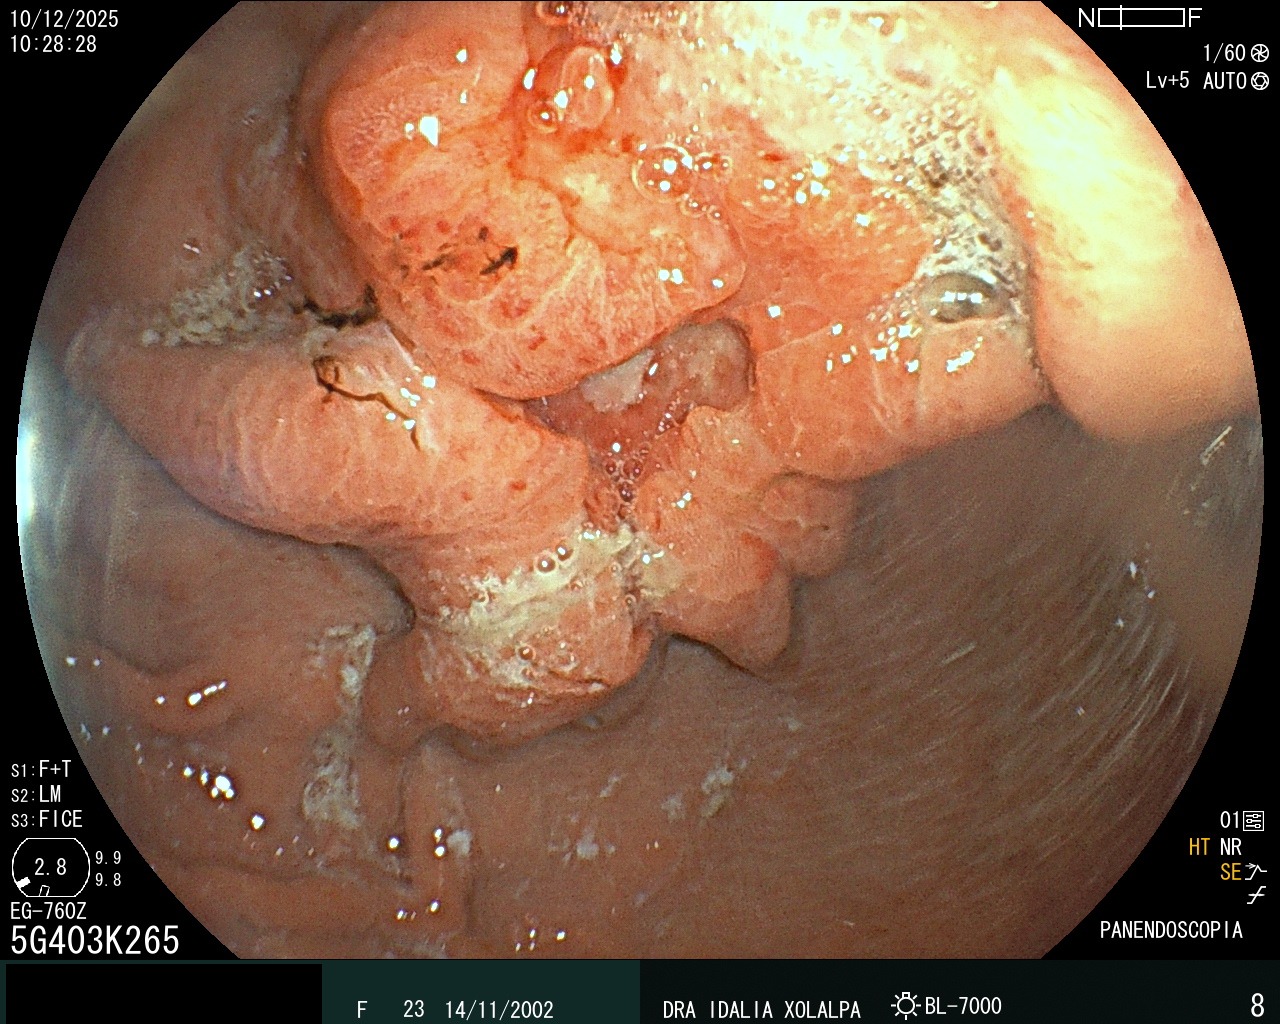

Detección de Tumores

Detección temprana de tumores en colon

Tumor Gástrico

Detección de tumor gástrico por panendoscopia